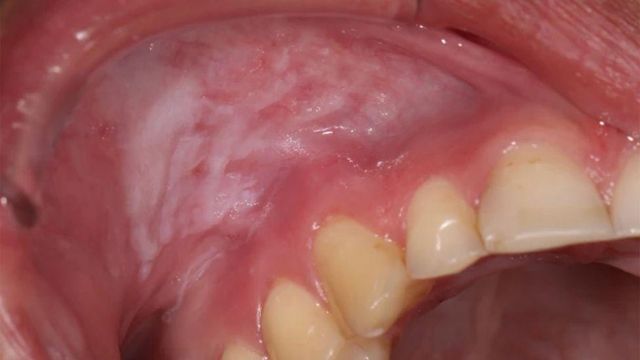

니코틴 파우치로 인해 손상된 잇몸

Sintija Miļuna-Meldere

반복적인 니코틴 파우치 사용으로 인해 생긴 흰색 병변

파우치가 잇몸에 미치는 손상에 대한 우려 또한 점점 커지고 있다.

니코틴 파우치를 1년 넘게 사용해 온 핀은 결국 "입 안이 완전히 너덜너덜"해졌으며, 한 번은 "잇몸의 절반이 벗겨졌다"고 말했다.

영국 본머스에 있는 스웨덴 출신 치과의사 패트릭 사라비 박사는, 파우치를 사용하는 환자들 중 일부가 치아 뿌리가 보일 정도로 깊은 잇몸 병변을 겪는 사례를 치료해 오고 있다.

그는 "니코틴 파우치가 장기적으로 끼치는 손상은 정말 심각한 우려를 낳고 있다"고 말했다.

그의 환자 중 한 명인 23세 대학생은 전자담배를 끊기 위한 시도이자 공부에 집중하기 위한 수단으로 시험공부를 하며 하루에 파우치를 5개씩 사용했다. 그러다 잇몸에 병변이 생기기 시작했다.

이 환자는 "처음엔 그냥 재미로 시작했다"며 "그런데 금방 중독됐다"고 말했다.

"파우치를 대던 잇몸의 살점이 떨어져 나간 걸 보고 나서야 심각성을 깨달았어요."

니코틴 파우치에 대해 2년간 연구를 해 온 사라비 박사는 이 제품이 국소성 치주질환과 국소성 골손실 위험을 높인다고 설명했다.